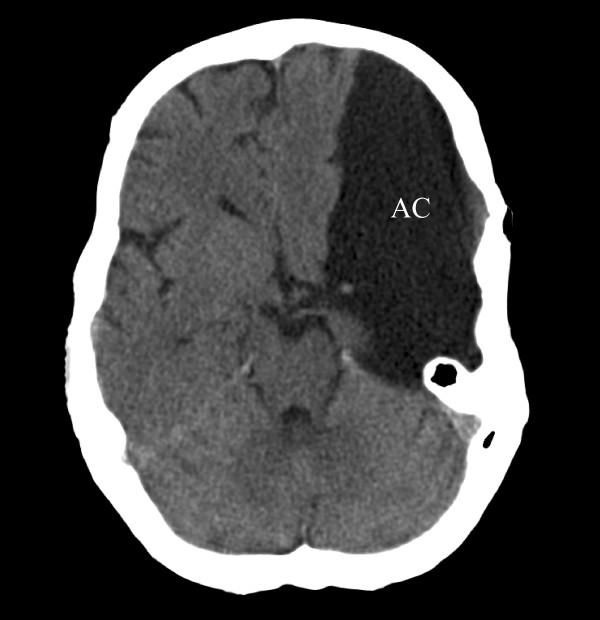

Intracranial arachnoid cysts (AC) are membranous sacs filled with CSF-like fluid that are commonly found in the temporal fossa. The majority of ACs are congenital. Typical symptoms are headache, dizziness, and dyscognition. Little is known about genes that contribute to the formation of the cyst membranes.

颅内蛛网膜囊肿(AC)是充满脑脊液样液体的膜性囊,常见于颞窝。大多数AC是先天性的。典型症状为头痛、头晕和认知障碍。关于促成囊肿膜形成的基因知之甚少。